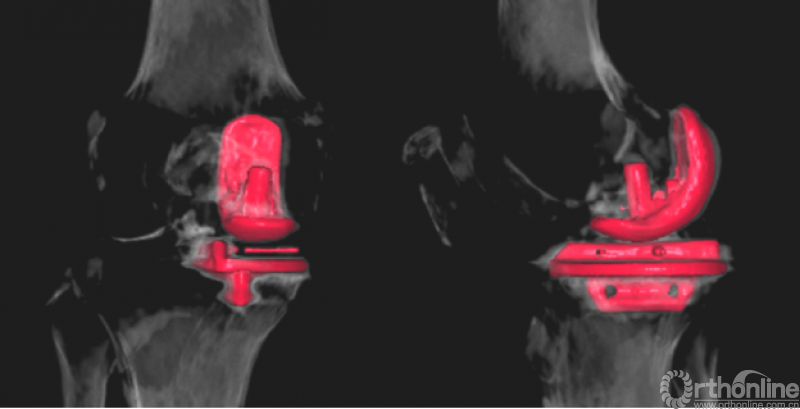

测量胫骨截骨块和胫骨假体的前后(AP)和内外(ML)长度,并计算ML/AP比值。对胫骨截骨块和胫骨假体的AP、ML、ML/AP进行组内和组间比较。术后通过X线和CT评估胫骨假体的内外侧位置和外旋角度,并进行组间对比。

结果表明FAMA线与Akagi线基本平行,其夹角为4.272±0.552°。胫骨截骨块和胫骨假体的AP、ML长度无显著差异(AP差值0.007±0.154cm,p=0.674,ML差值0.020±0.195cm,p=0.155)。两组间的AP、ML长度无显著差异(AP:p=0.281,0.741,0.672,0.849,0.287;ML:p=0.3,0.866,0.085,0.255,0.09;假体型号由AA至D)。两组间的ML/AP比值无显著差异(p=0.141,0.646,0.255,0.607,0.384;假体型号由AA至D)。两组胫骨假体的内外侧位置(组1:0.87±0.03,组2:0.86±0.03,p=0.156)和外旋角度(组1:6.88±2.08°,组2:6.68±2.22°,p=0.746)无显著差异。

4、术后影像学检查示,假体覆盖良好,假体外侧缘与Akagi线基本平行,未出现过度旋转。